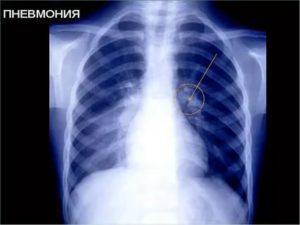

- Рентгенография грудной клетки – наиболее информативный способ выявление воспалительных процессов в легких (на снимках появляются характерные затемнения в местах поражения тканей и другие признаки заболевания);

Для постановки диагноза необходимо сделать рентгенограмму легких, а также сдать анализы крови и (при необходимости) мокроты. Кашель на ранних стадиях проявляется не у всех.